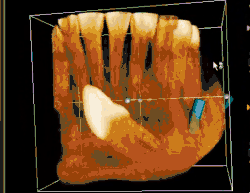

Angulation of tooth

Most commonly used classification system with respect to treatment planning. Depending on the angulation the tooth might be classified as:

- Mesioangular

- Horizontal

- Vertical

- Distoangular

- Palatal

- Buccal

- Lingual